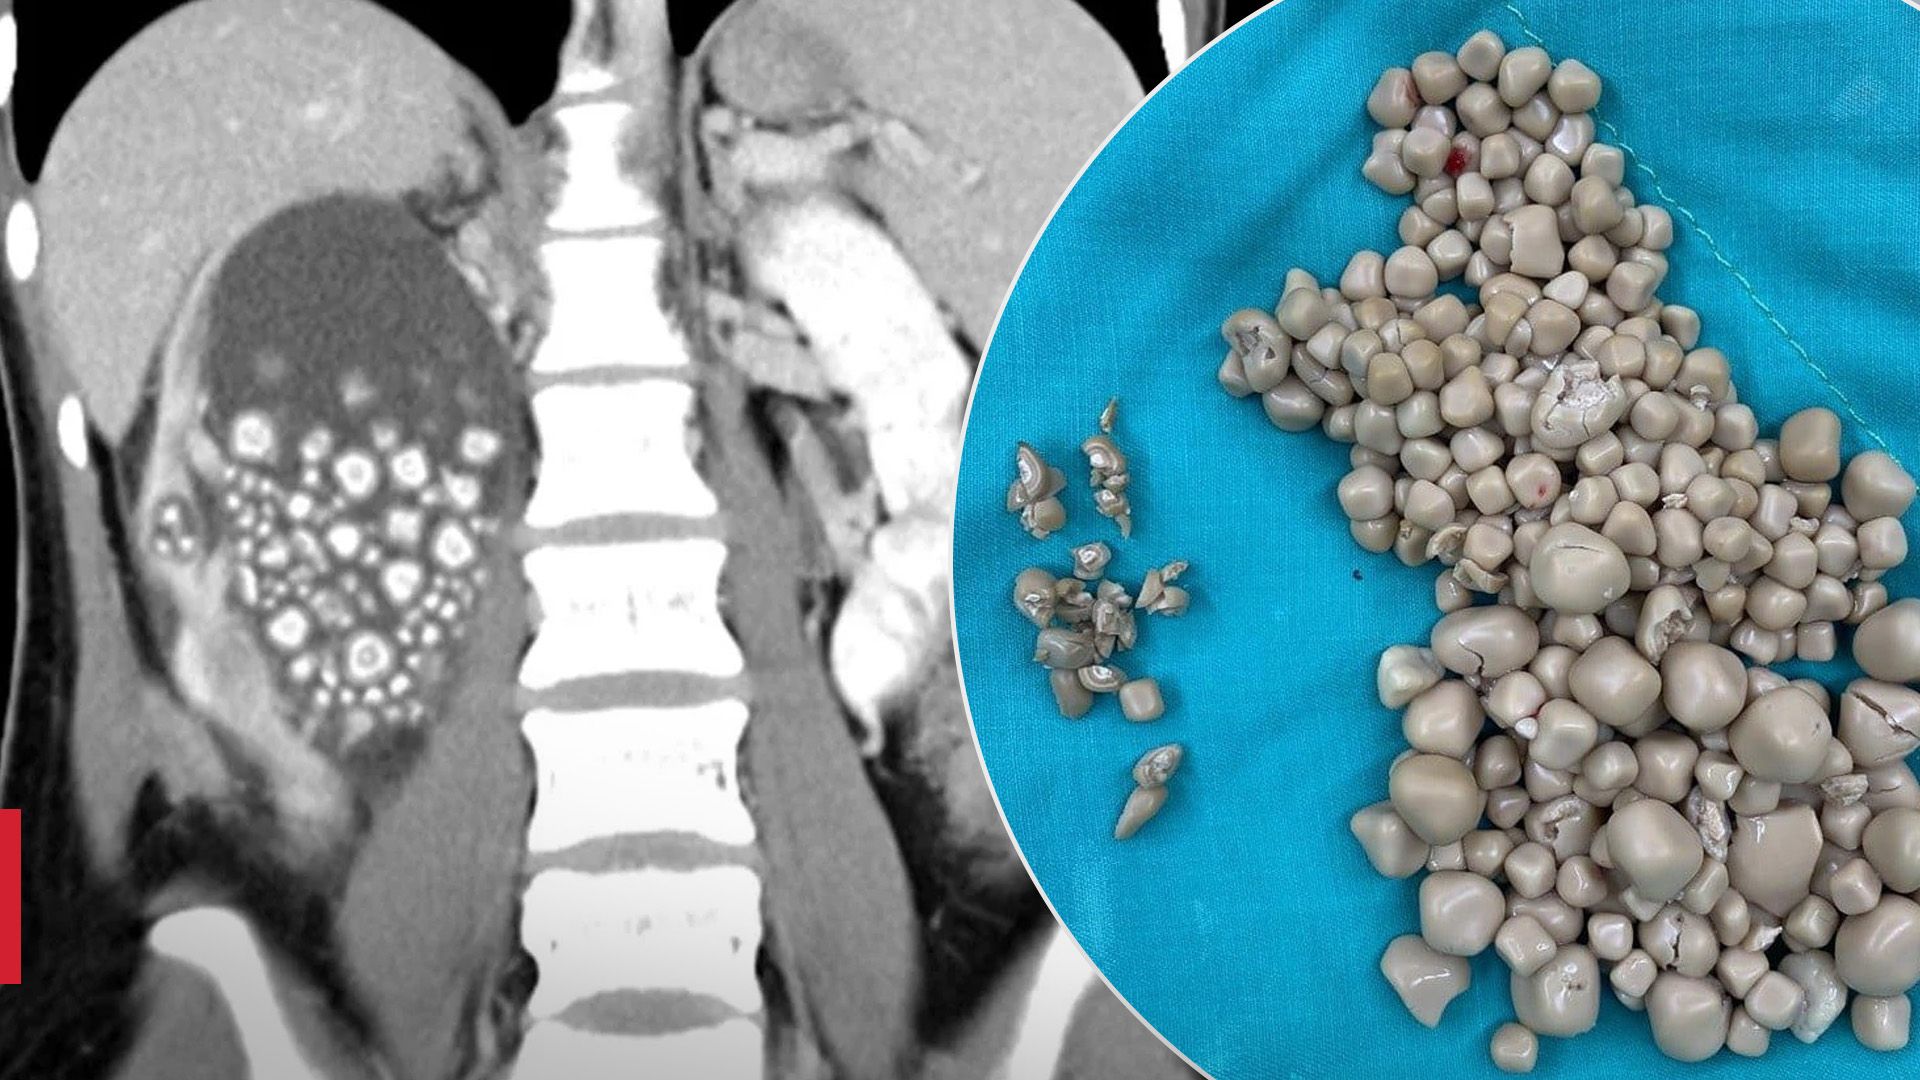

Уже під час комп'ютерної томографії лікарі побачили, що права нирка дівчини просто переповнена каміннями.

На МРТ лікарі побачили, що у нирці скупчилась рідина і камені / Фото Oddity Central

Під час операції лікарі витягли понад 300 каменів розміром від 5 міліметрів до 2 сантиметрів.

Лікарі дістали з нирки дівчини понад 300 каменів / Фото Oddity Central